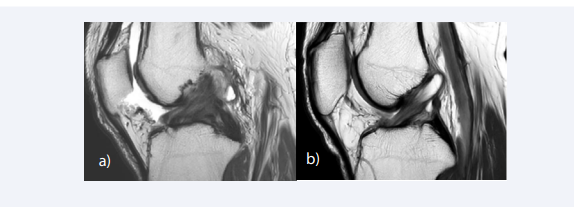

MR findings of ACL injury can be divided into primary signs related to the changes of the ACL itself, and secondary signs related to changes in the surrounding structures. The most reliable primary sign of acute ACL tear is the discontinuity of the ligament fibers, and the failure of the ACL fascicles to parallel the Blumensaat line on sagittal image [54] (Figure 2A).

Primary and secondary signs of ACL tear. (A) Sagittal T2-weighted image shows discontinuity of the ACL at the mid-substance indicating a complete tear. (B)  Sagittal fat-suppressed proton density-weighted shows diffuse enlargement and cloud-like hyperintense signal intensity of the ligament, resulting from edema and  hemorrhagic change of the ligament. (c) Sagittal image through the lateral compartment shows kissing bone contusion involving the posterior aspect of the lateral  tibial plateau and the mid portion of the lateral femoral condyle at the sulcus terminalis, which indicates a pivot shift injury. A slight depression fracture at the sulcus  terminalis of the lateral femoral condyle is noted (“deep notch sign”) (D) A thin fluid signal is interposed between the posterior horn of the medial meniscus and the  posteromedial capsule, leading to the diagnosis of meniscal ramp lesion associated with ACL tear.

Figure 2: Primary and secondary signs of ACL tear. (A) Sagittal T2-weighted image shows discontinuity of the ACL at the mid-substance indicating a complete tear. (B) Sagittal fat-suppressed proton density-weighted shows diffuse enlargement and cloud-like hyperintense signal intensity of the ligament, resulting from edema and hemorrhagic change of the ligament. (c) Sagittal image through the lateral compartment shows kissing bone contusion involving the posterior aspect of the lateral tibial plateau and the mid portion of the lateral femoral condyle at the sulcus terminalis, which indicates a pivot shift injury. A slight depression fracture at the sulcus terminalis of the lateral femoral condyle is noted (“deep notch sign”) (D) A thin fluid signal is interposed between the posterior horn of the medial meniscus and the posteromedial capsule, leading to the diagnosis of meniscal ramp lesion associated with ACL tear.

The ligament fibers may be edematous and hemorrhagic resulting in diffuse enlargement and cloud-like hyperintense T2 signal in the acute to subacute phase [55] (Figure 2B). The proximal stump of the torn ACL is usually oriented more vertically, and the distal stump more horizontally compared with the Blumensaat line. Nonvisualization of the ACL fibers is a common and specific finding of chronic complete tear of the ACL, resulting in an empty intercondylar notch [56, 57]. Another common finding of chronic ACL injury is a thin residual fiber demonstrating an abnormal slop. Occasionally, a chronic tear may be mistaken for an intact ligament, due to the fibrous scar that bridges the proximal and distal stumps giving the ACL a continuous appearance [55].

Various secondary signs may aid the diagnosis of ACL tears; anterior translation of the tibia, uncovering of the posterior horn of the lateral meniscus, buckling of the PCL, characteristic bone contusion patterns, and Segond fracture. Anterior translation of the tibia with reference to the femur is a helpful finding in diagnosing complete tears of the ACL [58] (Figure 3).

The degree of translation can be measured in the lateral compartment on sagittal images, as the distance between the posterior margin of the proximal tibia and the posterior margin of the lateral femoral condyle. Translation of 5mm or greater has been reported to show a sensitivity of 86% and specificity of 99% for ACL tear [59]. Anterior translation may lead to uncovering of the posterior horn of the lateral meniscus, and buckling of the PCL [60].

The pattern of bone contusions depends on the mechanism of injury and can be helpful in diagnosing associated injuries of the meniscus and other ligamentous structures. The most common bone contusion pattern is the kissing bone contusion involving the posterior aspect of the lateral tibial plateau and the mid portion of the lateral femoral condyle at the sulcus terminalis, which is associated with pivot shift injury [16] (Figure 2C). Pivot shift reciprocating bone contusions indicate the impaction of the femoral condyle on the posterior aspect of the tibial plateau during anterior translation. Less commonly, bone contusions can be noted along the posterior aspect of the medial tibial plateau and the medial femoral condyle. Contusions of the medial compartment are thought to result from a contrecoup injury at the point of reduction [17]. Stronger compressive forces at the time of injury may cause cortical depression fractures in the tibia and femur. A depression fracture at the sulcus terminalis of the lateral femoral condyle is termed “deep notch sign” and is known as an indirect sign of acute ACL tear [61] (Figure 2C). With a depth cut-off of 1.5mm, the deep notch sign has a specificity of 100%, sensitivity of 15.4%, positive and negative predictive value of 100% and 49.1% respectively [62]. The deep notch sign was originally described on radiograph but can also be noted on MRI [63].